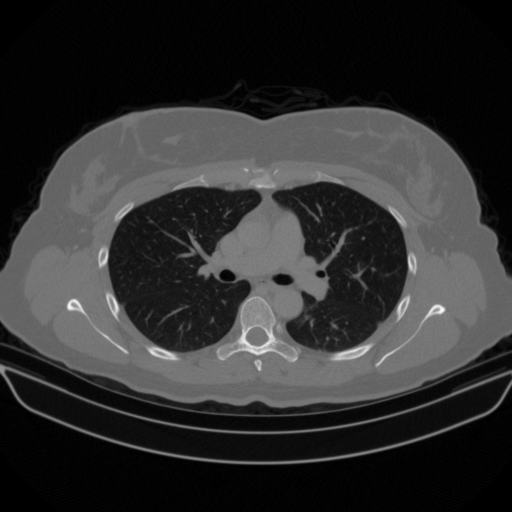

Targeted Slice 70 - Network-Normalized Analysis (Generated vs Real Venous)

0.885

SSIM Score

0.092

RMSE

0.040

MAE

Average Network-Normalized Metrics Across All Slices (38 slices) - Generated vs Real Venous

0.887

SSIM Score (Avg)

0.097

RMSE (Avg)

0.041

MAE (Avg)

Original VENOUS CT scan

No window - Raw intensity values

Lung window (WL -600, WW 1500 β†’ Low βˆ’1350, High +150)